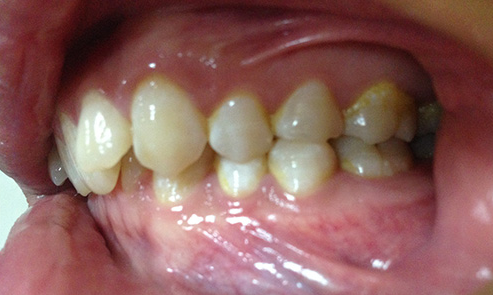

我们把牙齿在咬牙时,下牙被上牙全部盖住,或只露出很少的一部分,则可以判断为深覆合。

深覆合侧面